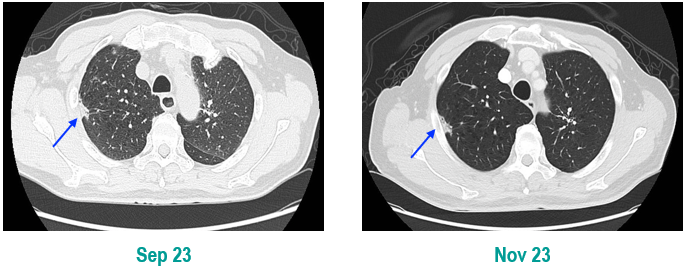

PET-CT(2023年9月):右下肺叶发现6.9×6.7×6.6cm的FDG高摄取肿块,伴右侧第7、8肋骨侵犯可疑,右肺门淋巴结肿大,双肺上叶多发结节,考虑腺癌谱系疾病。

CT及PET-CT随访(2023年11月、2024年1月):评估新辅助治疗效果,右下肺叶肿块缩小,右肺门淋巴结代谢活性消失,右肺上叶结节稳定但代谢活性降低,左肺上叶及双侧磨玻璃样病变稳定。